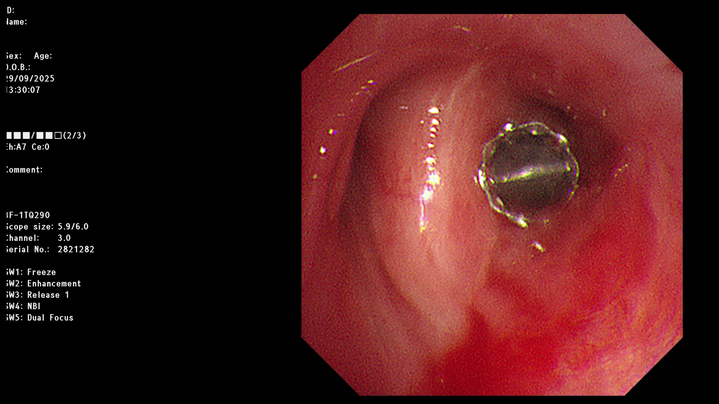

图为置入活瓣后

在明确治疗方案并与患者及家属充分沟通后,丁明团队决定实施经支气管镜EBV活瓣封堵术。手术在气管镜引导下进行,根据术前测量的结果,术中仅通过气管镜工作通道便将输送导管准确送到目标支气管,然后推动推送器将一枚直径4毫米的活瓣精准置入右上叶后段支气管开口。

这枚形似“鱼嘴”的活瓣暗藏玄机:它能随呼吸周期实现单向闭合,吸气时严密关闭阻止气体进入瘘口区域,呼气时则自动打开允许气体排出,形成“只出不进”的气流模式,从而维持胸腔负压,为瘘口愈合创造条件。置入瞬间,医护人员便观察到引流瓶水柱停止波动——这意味着漏气已即刻终止。